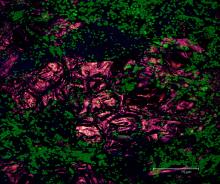

Rat brain section